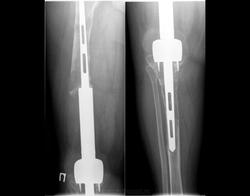

Все снимки сделаны через 10-30 лет после эндопротезирования

Снимки 4,5,6 пациентки, которой была сделана резекция бедренной кости с эндопротезированием коленного сустава 30 лет назад по поводу остеосаркомы. Расшатывание эндопротеза клинически стало себя проявлять 5 лет назад (снимок 4), далее довольно быстро прогрессировало, что по-видимому усугубилось присоединившимся остеомиелитом (снимки 5, 6 - теперешние). Пришлось выполнить ампутацию, тем не менее, человеку дали 25 лет нормальной, полноценной жизни.